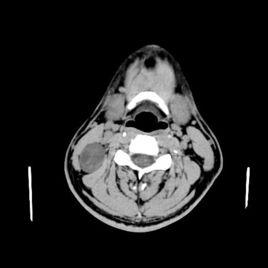

本書作者從正常解剖、病理生理到常見病、罕見病,對每一個疾病從術語、影像表現、鑑別診斷、病理、臨床、鑑別要點等都做了摘要性描述,全書提綱挈領,簡明扼要,重點突出,易於通讀;對常見HRCT徵象也分類做了詳細闡述,羅列了每一徵象的常見疾病,對鑑別診斷非常有幫助。本書的另一個特點是圖文並茂,本書不僅有X線、CT圖片,還有很多彩色病理圖片及線條圖,對理解疾病的發生、發展及與影像表現的關係非常有幫助